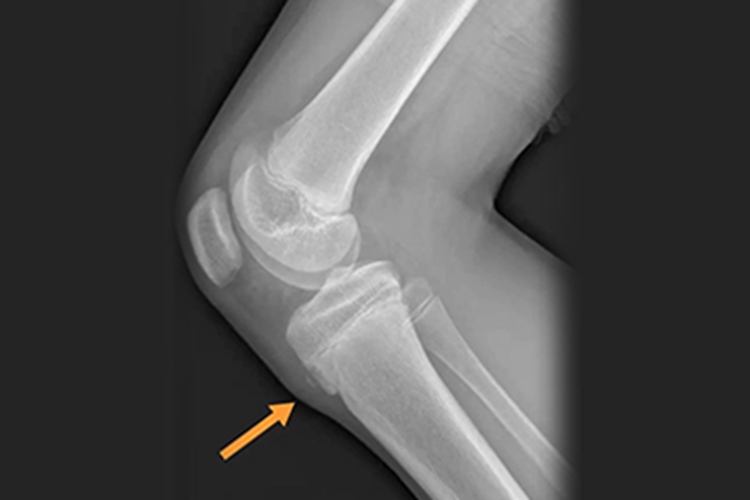

胫骨结节炎临床表现为膝痛,行走时明显,上下楼梯时加重。X线片显示胫骨结节骨骺呈舌状,骨骺骨质致密,或骨骺边缘不规则,附近软组织肥厚,或见骨骺碎裂与骨干分离。体格检查发现一侧或双侧胫骨结节上端前方局限性肿胀,压痛明显,晚期胫骨结节肥大突起,对股四头肌抵抗阻力运动引起局部疼痛加重。